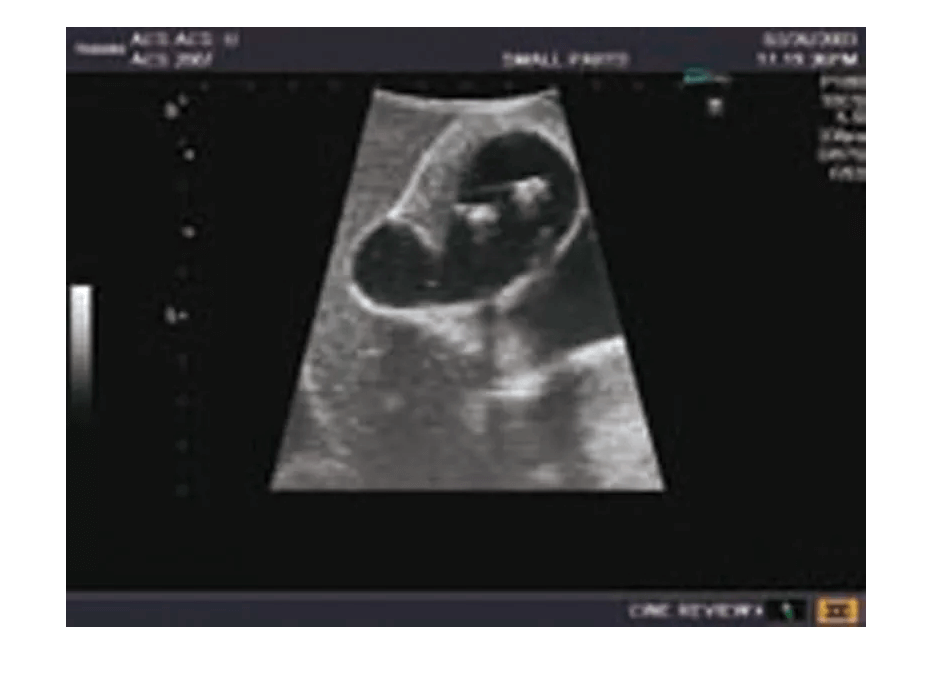

Das Ultraschall-Modell für Sonografie ist speziell für die Ausbildung von Anfängern und die Demonstration durch Fachleute konzipiert. Es bietet eine detaillierte und realistische Darstellung der Anatomie des Abdomens, einschließlich der Leber, Gallenwege, des Pankreas und der Nieren. Das Modell erfüllt die höchsten Anforderungen an eine exzellente Ausbildung und ermöglicht die Durchführung von offenen intraoperativen Sonografien sowie laparoskopischen Untersuchungen, um etwaige Läsionen und Steinbildungen zu prüfen. Es umfasst eine Vielzahl von Läsionen wie Gallensteine, Zysten und Tumore, die in den verschiedenen Organen simuliert sind, um realistische Übungsmöglichkeiten zu bieten.

Simulierte Läsionen (solide Tumore, Zysten, Gallensteine) in wichtigen Organen für praxisnahe Ausbildung

Die Simulation von pathologischen Befunden wie Tumoren, Zysten und Steinbildungen ermöglicht eine umfassende Vorbereitung auf die Ultraschalldiagnostik